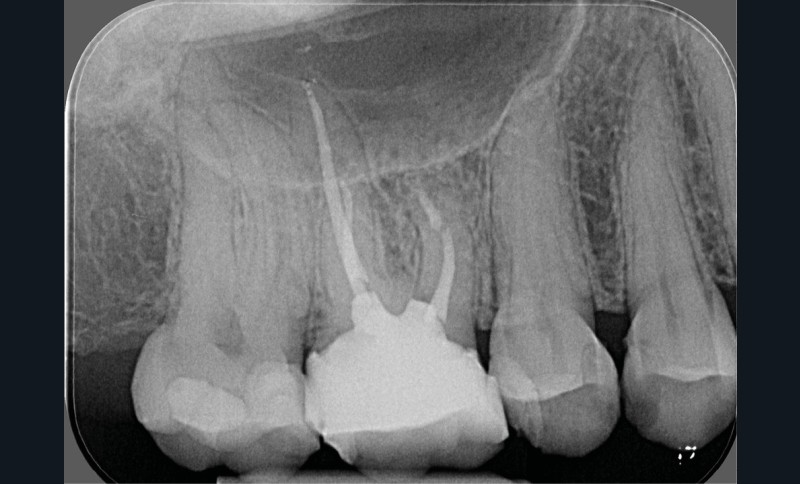

- une pathologie péri-radiculaire ne guérit pas à la suite d’un (re)traitement (fig. 1a-b) ;